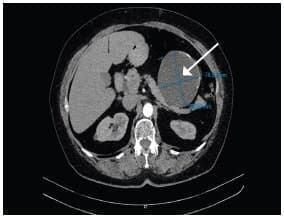

Se realizó una ecografía de abdomen total que informó una imagen quística de 8 x 7 cm, en íntimo contacto con la cola del páncreas. Posteriormente una tomografía computarizada de abdomen con contraste reportó una lesión hipodensa de aspecto quístico, de 86,6 x 78,5 mm, en contacto con la curvatura mayor del estómago, el cuerpo y la cola del páncreas, con paredes irregularmente engrosadas y calcificaciones periféricas aisladas en su interior.

Como primera posibilidad se sugirió un tumor del estroma gastrointestinal (GIST, por sus siglas en inglés) (figuras 1 y 2). La endoscopia de vías digestivas altas diagnosticó una gastropatía antrocorporal no erosiva sin hallazgos patológicos adicionales.

Figura 1. Corte axial de tomografía computarizada contrastada de abdomen (plano transverso).

Se señala la lesión hipodensa de aspecto quístico de 86.6 mm x 78.5 mm